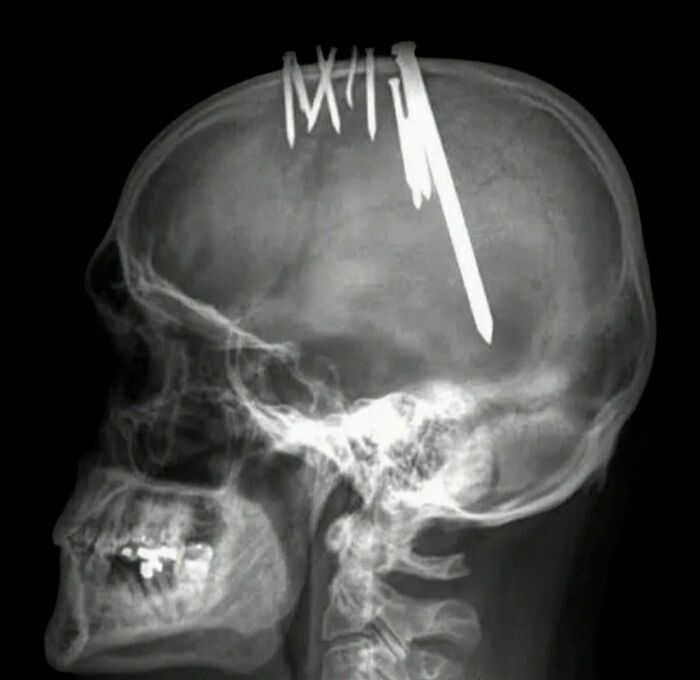

44-year-old man came to the emergency department wearing a baseball cap and complaining of severe headaches that had progressively worsened over the preceding 11 weeks. when the patient removed his cap to it was revealed that an assortment of metallic objects are embedded in his scalp.

Plain radiographs showed 11 nails penetrating into his brain. His detailed history presented a diagnosis of PARAN0ID SCHlZ0PHRENlA, and the patient confirmed that he had hammered a nail into his head each week for the past 11 weeks in order to rid him of evil.

The nails were removed with the patient under general anesthesia, and he made an uncomplicated recovery with no neurological deficits.